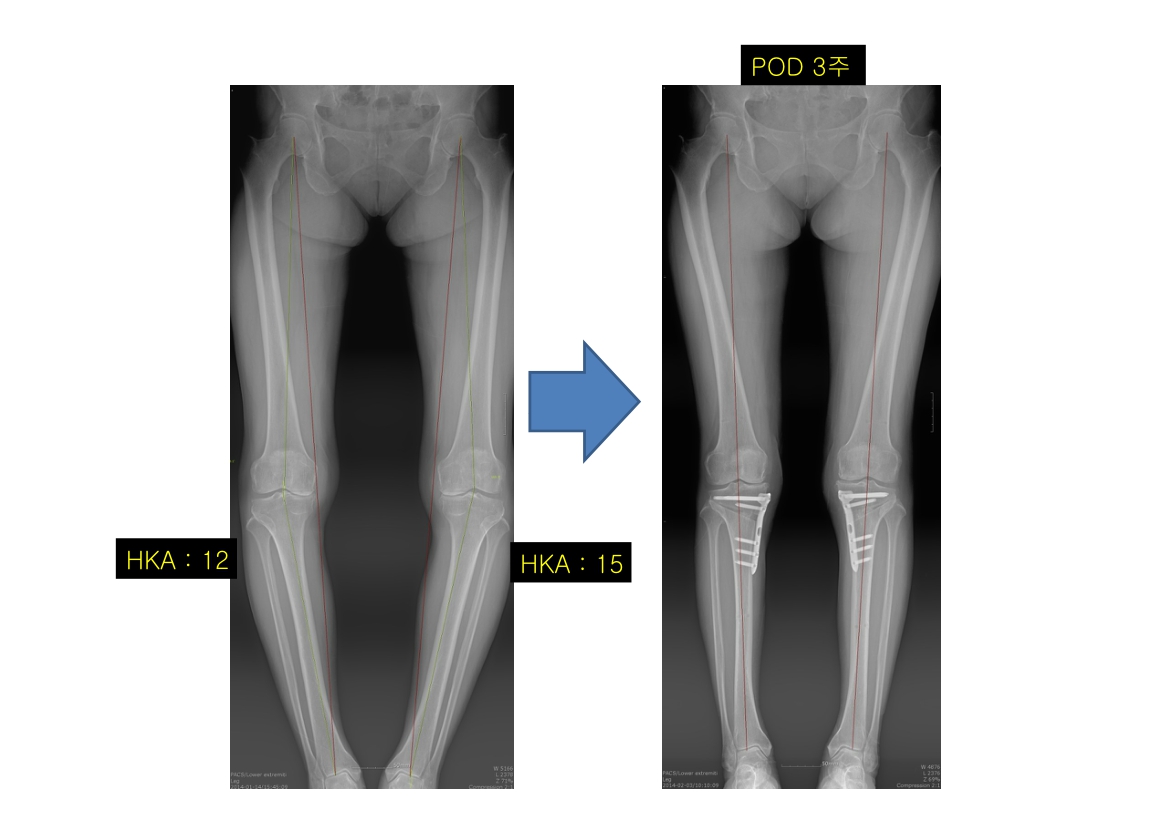

윤정로 병원장님 퇴행성 관절염 치료 자료

윤정로 병원장님의 퇴행성 관절염 치료 관련 자료 입니다.